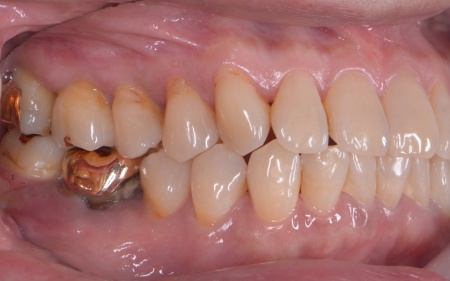

| カウンセリング | 拝見したところ、上下左右の奥歯計8本(第1大臼歯、第2大臼歯)に重度の歯周病が認められました。 歯周病は歯を支えている骨や歯ぐきに炎症が起こる病気です。進行すると歯がぐらついたり、噛む力が弱くなったりします。 さらに悪化すると歯を失う可能性が高くなるだけでなく、周囲の歯にも影響が広がることがあります。 特に下の奥歯2本(左右第1大臼歯)は歯を支えている骨が著しく減少して歯が大きく揺れており、治療して温存することは難しい状態でした。 また、左上の奥歯(第1大臼歯)は過去に詰め物で治療されていましたが、その下で虫歯が再発しています。 以上のことから、下左右の第1大臼歯は抜歯後に歯を補う治療、その他奥歯の治療、再発した虫歯の治療が必要と診断しました。 |

インプラント治療は、周囲の歯を削ることなく失った歯の部分のみを単独で補うことができます。 ただし、外科手術が必要となり治療期間が比較的長くなる点がデメリットです。 次に歯周病が認められるその他の奥歯については、歯周組織再生療法を行いできるだけ歯を抜かずに残す方法を提案しました。

さらに虫歯が再発していた左上奥歯については、虫歯をしっかりと取り除いたうえで被せ物による修復治療を提案しました。 それぞれのメリット・デメリットを丁寧に説明したところ、治療計画に同意いただきました。 まず、歯周基本治療から開始しました。 下左右の第1大臼歯を抜歯し、その部位にインプラントを埋め込む手術を行いました。同時に、インプラントの隣にある下の第2大臼歯に対して歯周組織再生療法を施しています。 また、左上の奥歯は虫歯を取り除いたあと、歯の形を整えて型取りを行い、最終的にジルコニアクラウンを装着しています。 段階的に治療を進め、すべての治療を終了しました。 |